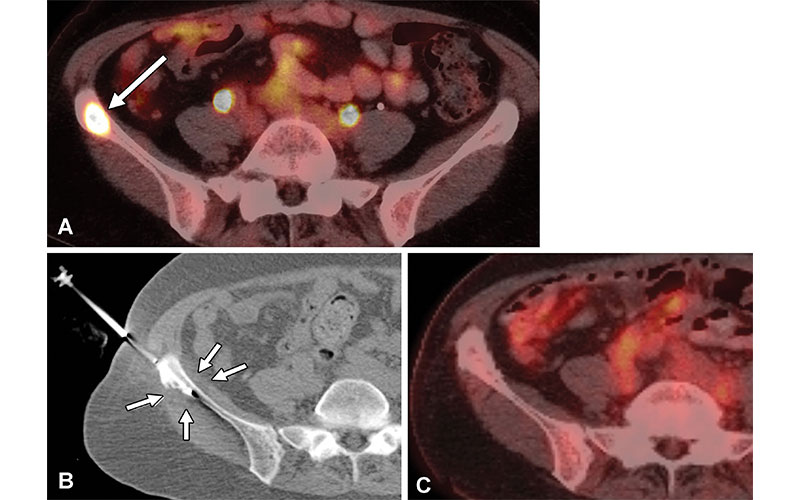

Контроль опухоли у 61-летней женщины с трижды положительным метастатическим раком молочной железы и болезненным метастатическим поражением правой подвздошной кости. Криоаблацию выполняли для облегчения боли и локального контроля опухоли. (A) Аксиальное изображение фтордезоксиглюкозы (ФДГ) с фтором 18 (18F) показывает гиперметаболическое метастатическое поражение правой подвздошной кости (стрелка). (B) На аксиальном КТ-изображении лежа на спине, полученном во время криоаблации, показано размещение криозонда (всего было установлено два криозонда) в метастатическом поражении с гипоаттенуирующим ледяным шаром (стрелки), охватывающим неопластическую ткань и распространяющимся на соседние мягкие ткани для обеспечения местного контроль опухоли. (C) Аксиальное изображение ПЭТ/КТ с 18F-FDG, полученное через 3 года после криоаблации, показывает локальный контроль над опухолью и отсутствие признаков рецидива опухоли. https://doi.org/10.1148/rg.220009 © РОСНА 2022